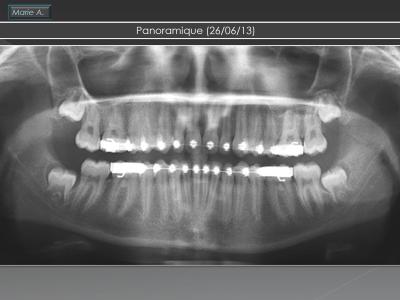

Traitement

Ce traitement a duré 24 mois avec :

Première phase DDEU constitué de :

- sectoriel .019’’x.025’’ acier

- arc lingual .036’’

- élastique 3 oz maximum portées 23h/24

Deuxième phase multi-attaches arc droit

Contention